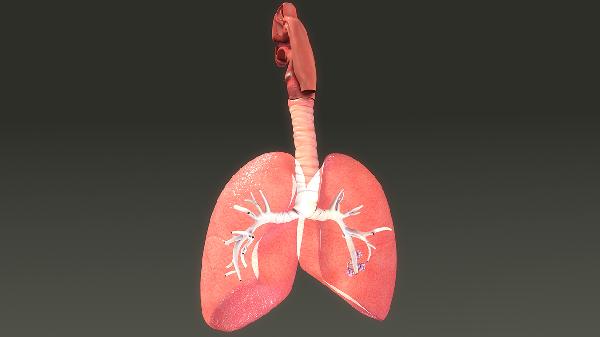

病毒性肺炎的药物飞龙app游戏主要包括抗病毒药物、解热镇痛药、祛痰止咳药、免疫调节剂和中药制剂。

病毒性肺炎患者应保持每日2000毫升以上饮水量,选择百合银耳羹等润肺食疗。恢复期进行腹式呼吸训练,避免剧烈运动。居室湿度维持在50%-60%,定期开窗通风。出现呼吸急促、血氧饱和度低于93%需立即就医。老年患者需监测心率血压变化,儿童注意观察精神状态和进食情况。